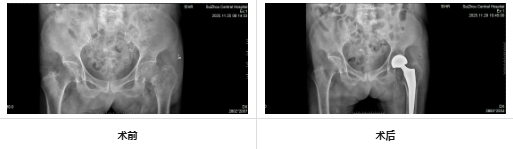

錦旗上“成功置換 人造股骨頸”九個字背后,是一段關(guān)于信任與專業(yè)的醫(yī)患故事。老人的老伴患有尿毒癥晚期,又遭遇股骨頸骨折,深受疼痛困擾,日常活動舉步維艱。因患者高齡且基礎(chǔ)病復(fù)雜,手術(shù)風(fēng)險高,多家醫(yī)院評估后均顯謹(jǐn)慎。

在充分的術(shù)前準(zhǔn)備與精細(xì)的術(shù)中操作下,團(tuán)隊(duì)成功為患者實(shí)施人工髖關(guān)節(jié)置換術(shù)。手術(shù)時間短、出血少,極大減輕了患者身體負(fù)擔(dān)。術(shù)后,在護(hù)理團(tuán)隊(duì)的精心照護(hù)與康復(fù)指導(dǎo)下,老人恢復(fù)良好,疼痛顯著緩解,生活質(zhì)量大幅提升??粗习橹芈缎θ?,老先生感激滿懷。